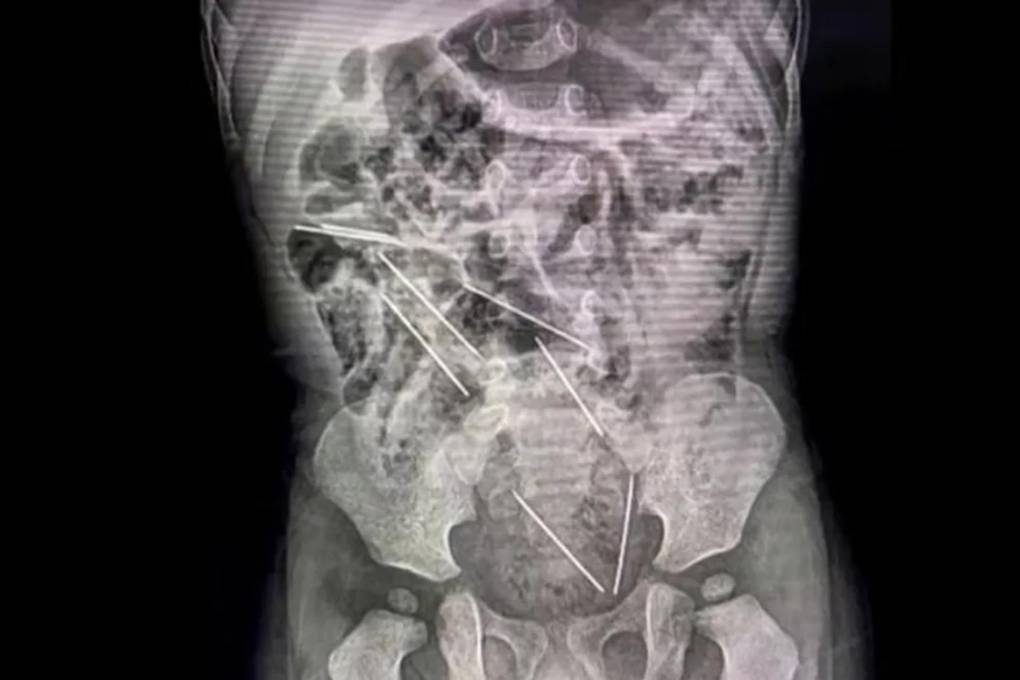

A través de una radiografía los médicos mostraron la cantidad de agujas que un niño de dos años ingirió accidentalmente.

Radiografía del estómago de un niño que se tragó ocho agujas

[Foto: Telecinco] / Radiografía del estómago de un niño que se tragó ocho agujas

Una radiografía mostró la cantidad de agujas que el niño ingirió y que según los médicos estaban comprometiendo el estómago y tracto intestinal, señaló un artículo de Telecinco. En total se encontraron ocho agujas del número 2 para inyecciones.

Los doctores explicaron que las agujas estaban cortadas en la parte distal y encontraron dos en el peritoneo del lado derecho, una que entró en una cavidad abdominal, tres en el lado izquierdo , uno en la pared abdominal y dos estaban peligrosamente abajo entre la vejiga y el recto.